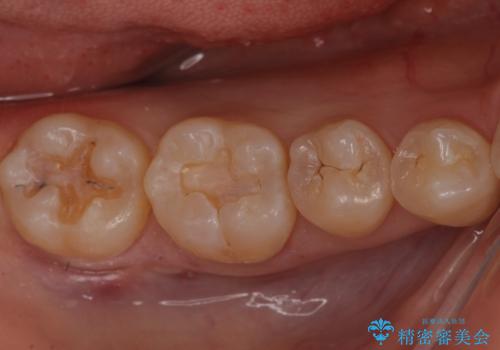

奥歯が黒く、心配。ゴールドインレーで修復

今回は、虫歯が進行したというよりは予防的な意味も含めて、金属で丈夫な適合の良いゴールドインレー(PGAインレー)による修復治療を行うことにしました。

- ゴールドインレー6万円 ×2本費用は治療当時の料金となります

ゴールドインレーによる修復は適合がよく、欠けることもなく、腐食もしにくく、アレルギーのリスクが極めて少ない安定した治療法です。ただし、セラミックと比較し目立つという欠点があるため、奥歯の力がかかるところにおすすめの治療法です。